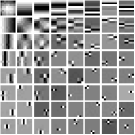

First, we study transform training based on Mayo Clinic data. As shown in Fig. 6, seven slices obtained at regular dose from three patients are used for transform learning. The number of pixels . Similar to the phantom experiments, overlapping patches are extracted with a patch stride. The number of overall training patches is about . We set for ST, , , for MARS2, , , , , for MARS3, , , , , , , , , for MARS5, , , , , , , , , , , , , for MARS7. The iteration number in Algorithm 1. Fig. 7 illustrates the learned transforms obtained with Mayo Clinic data. Different from the XCAT phantom case, these transforms up to MARS5 display more complex features and structures. The rich features of the MARS models better sparsify the training images over layers compared to the single-layer model (ST).